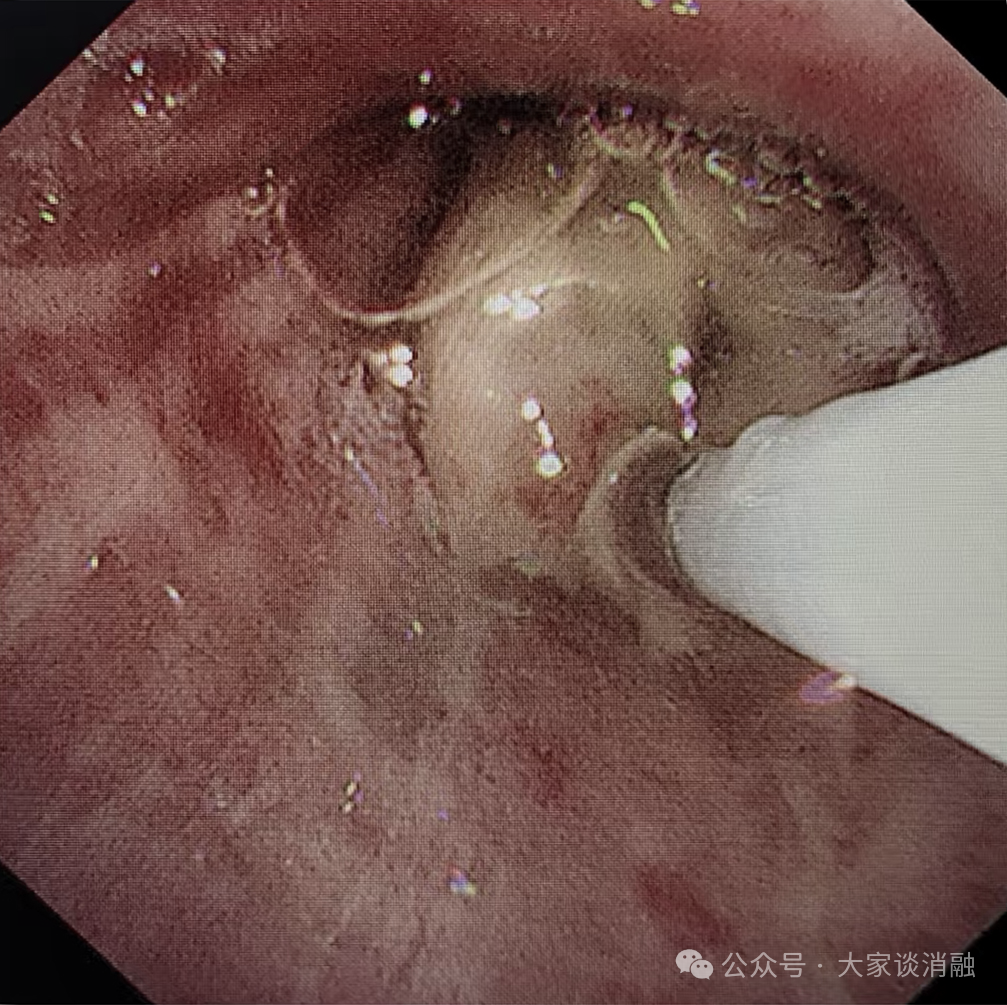

10月22日,患者接受第一次PTS治疗,在呼吸内二科邵桂英主任的精细操作下,全程顺利治疗后气道内肿瘤缩小达30%,患者呼吸困难症状大大缓解。

术前